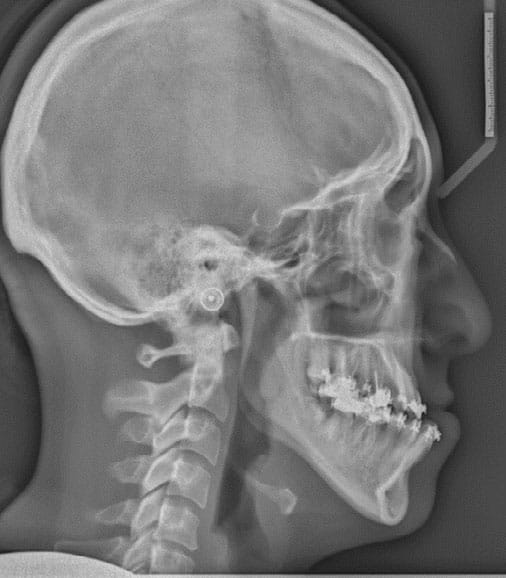

Return to "Understanding Orthognathic Surgery" FIGURE 8. Presurgical cephalometric radiograph demonstrating maxillary incisors in their original position, but mandibular incisors proclined to a Class I position. Notice the increase in negative overjet. Next Previous